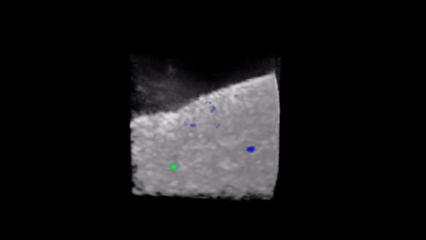

Densités de probabilité de présence de deux sphères métalliques enfouies dans une suspension granulaire ultra-diffusante superposées à une image échographique (noir et blanc) totalement brouillée. Chaque couleur correspond à un diamètre de sphère différent: 10 mm (bleu) et 8 mm (vert). Crédit image : Arthur Le Ber

L’idée des chercheurs [1] est d’exploiter les corrélations entre la matrice mesurée dans le brouillard et l’empreinte de référence. Ces corrélations permettent d’isoler les contributions spécifiques de la cible et de la faire apparaître, avec une précision meilleure que la longueur d’onde utilisée. Au lieu de corriger les effets du désordre – une tâche pratiquement impossible dans les milieux opaques –, la méthode révèle ce qui, dans le signal, résiste au brouillage. Pour valider ce principe, l’équipe a mené plusieurs expériences en acoustique ultrasonore. Des sphères métalliques enfouies dans une suspension granulaire, totalement invisibles par échographie conventionnelle, ont pu être localisées avec une fiabilité quasi certaine. Dans un second test, la méthode a permis de détecter des marqueurs de lésion utilisés en cancérologie mammaire, souvent difficiles à distinguer dans le bruit des tissus. Enfin, appliquée in vivo sur un mollet humain, elle a révélé l’architecture des fibres musculaires, ouvrant la voie à une imagerie quantitative des tissus, précieuse pour le diagnostic des maladies cardiaques ou neuromusculaires.